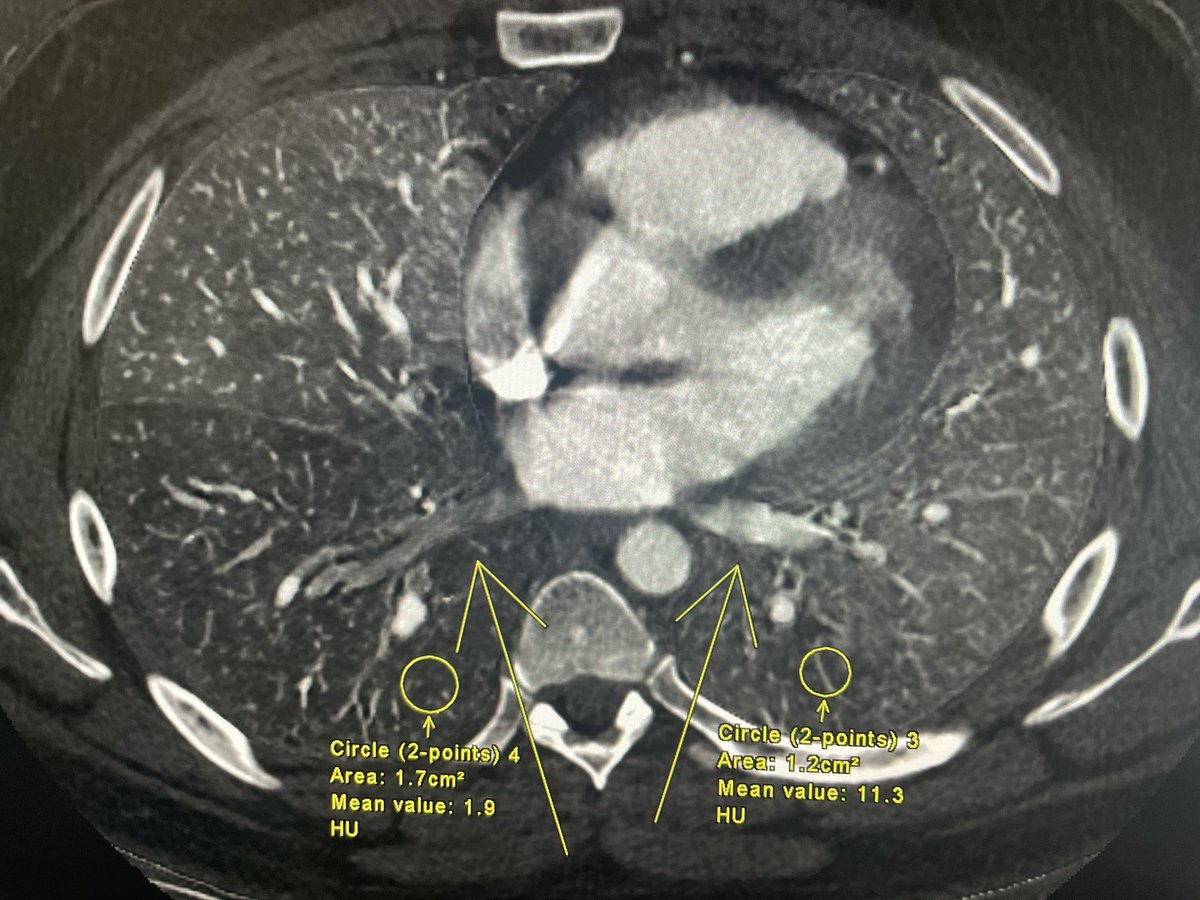

does show a iodine map perfusion defect and hypoperfusion of the right infer pulmonary vein (postcapillary). Patient went on to #firstecho and #whycmri showing gradient abnormalities in the RIPV…likely thrombus in the vein.

Giovanni_Lorenz's tweet image. does show a iodine map perfusion defect and hypoperfusion of the right infer pulmonary vein (postcapillary). Patient went on to #firstecho and #whycmri showing gradient abnormalities in the RIPV…likely thrombus in the vein.